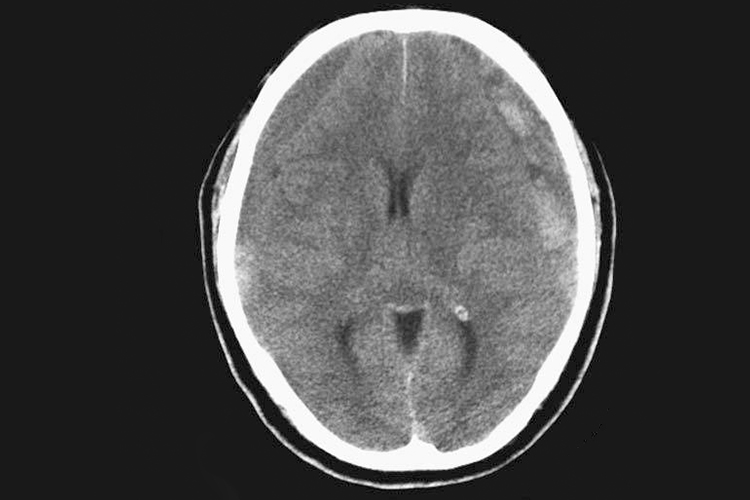

硬膜下血肿ct可见局部有高密度影,少数为等密度、低密度影。

硬膜下血肿的CT影像与发病类型有关,急性硬膜下血肿的CT大多表现为颅板下方的新月形高密度影,亚急性或慢性硬膜下血肿的CT可表现为高密度、等密度、低密度或混杂密度影。此外还常伴随昏迷、头痛、呕吐等症状。